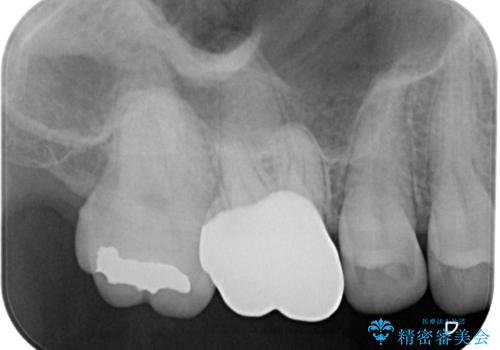

- 歯が割れたことを主訴に来院された患者様です。割れた原因としては噛み合う歯が強化セラミックスのみでできたフルジルコニアクラウンであったことと、大きな詰め物が入っていて自分自身の歯の範囲が少なかったことが考えられます。応急で来院されたときには暫間的に強力な接着剤で固定しました。

CT を撮影して確認したところ、歯肉より4ミリ程度深い場所で破折していました。患者様と相談して、外科的な介入はせずに被せもののみでの治療を行うこととしました。

拡大鏡視野下で詰め物と虫歯の除去を行い、詰め物の範囲が大きかったためオールセラミッククラウンに適した形に整えました。